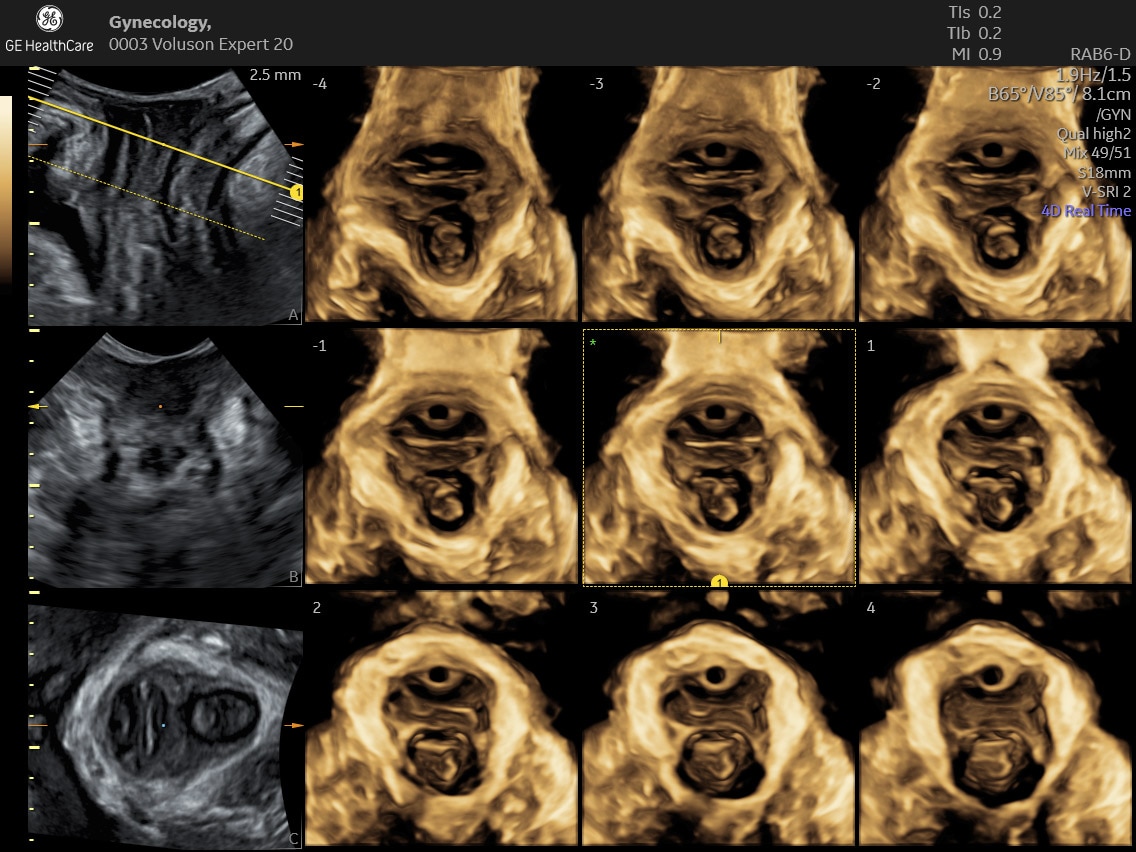

Amplify imaging performance and simplify scanning with our most advanced architecture

Refine Clinical Insights

Extraordinary clarity and definition so you can focus on early detection and intervention.

Faster.Sharper. Clearer.

Faster.Sharper. Clearer.